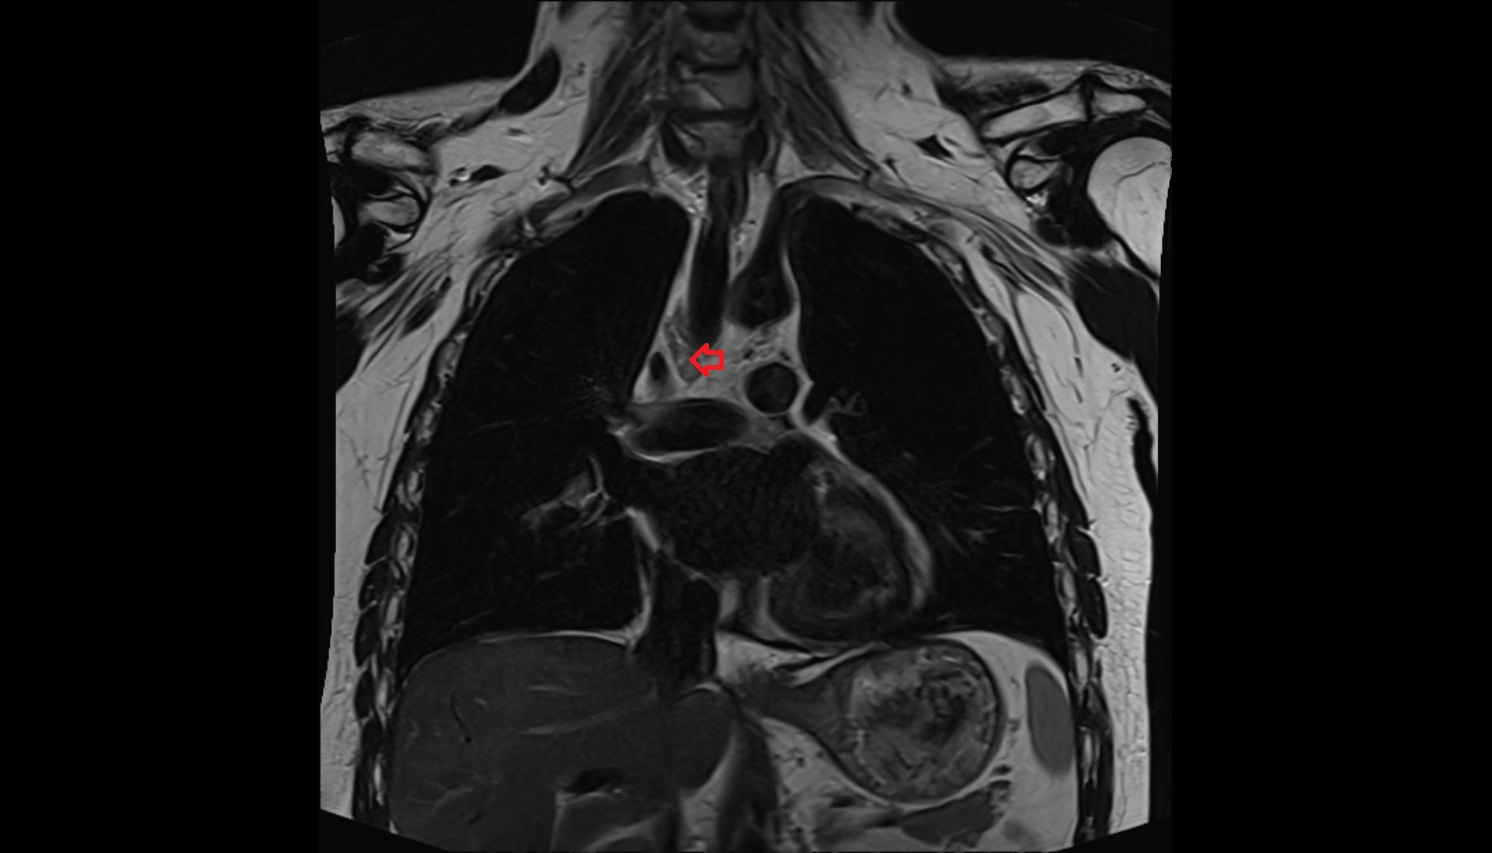

- Ascending aorta

- Arch of aorta

- Descending thoracic aorta